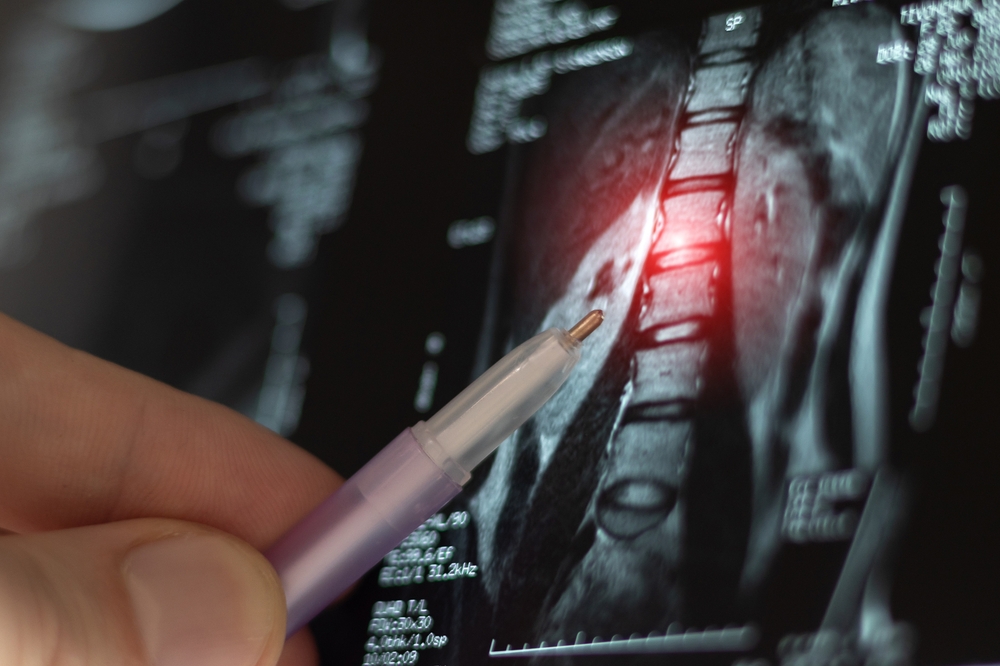

Spinal Tumors

Spinal tumors can be difficult to detect, but MRI excels in visualizing abnormalities along the spinal cord, nerves, and vertebrae. This helps neurosurgeons determine the best approach for treatment.